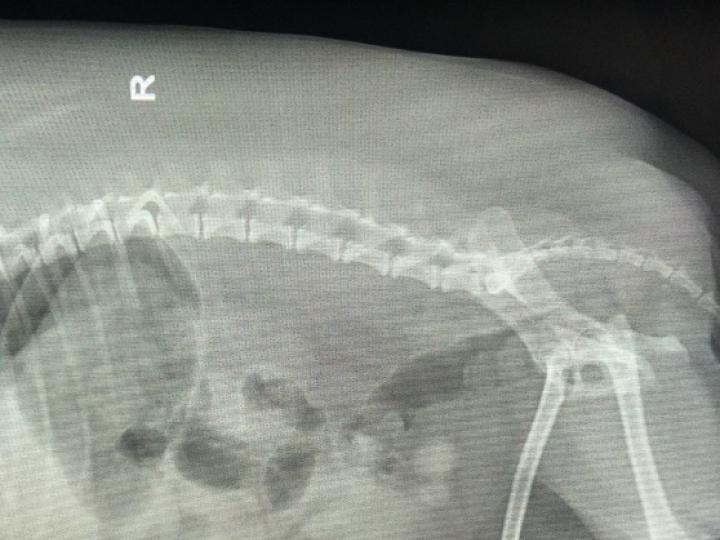

膀胱结石比较常见,特别是在宠物犬和猫身上,这个和它的饲养情况有关系,一般来说,像长期的饮水不足,这样会引起尿液的浓缩,使体内中的盐类浓度过高容易形成结石;吃钙磷比例不协调的食物,猫吃含镁量高的食物也容易形成结石;还有缺乏维生素A,引起细胞脱落形成结石的核心等。膀胱结石只是尿石症的一部分而且,还有常见的有肾结石,输尿管结石,尿道结石等。诊断的话,如果结石较大的话,可以通过腹部和直肠的触诊发现,必要的时候可以结合X射线检查,X射线检查比较简洁明了,可以看出哪个部分的结石情况,另外还可以进行尿液检查,分析尿中的成分,结石的类型。治疗的话可以根据结石的大小,位置,性别等做相适应的治疗措施。如果发现结石比较小的话,可以不用手术治疗,用一些利尿剂,多喝水,可以有助于结石排出来,还可以使用尿液的酸化剂,溶解结石,利于排出。另外的一种就是可以用手术治疗,这种适合结石大,不易排出的症状,手术护理的时候吃一些专门的食品来配合治疗,这样子恢复的更快。